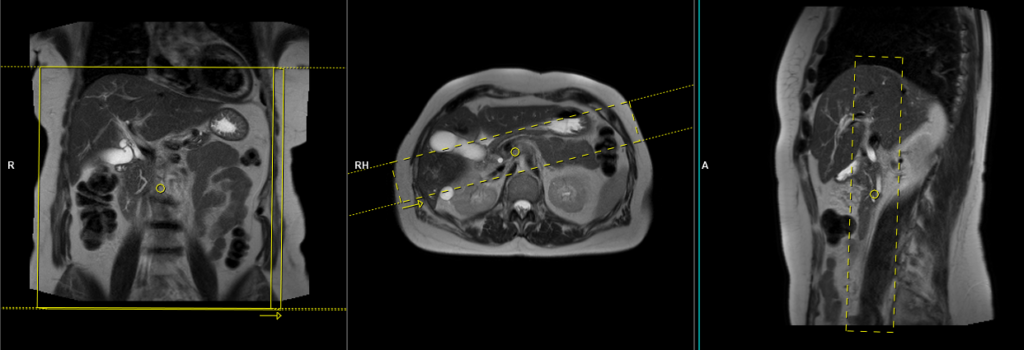

T2 HASTE 5 mm breath hold coronal

Plan the coronal slices on the axial localizer and position the block horizontally across the liver as depicted. Verify the position in the other two planes. Establish an appropriate angle in the sagittal plane, aligning it vertically across the liver. Ensure that the slices adequately cover the entire liver, extending from the anterior abdominal wall to the erector spinae muscles. The phase direction should be from right to left to minimize ghosting artifacts from the lungs and heart. Employ phase oversampling to prevent wrap-around artifacts. Instruct the patient to hold their breath during image acquisition. (In our department, we typically advise patients to breathe in and out twice before providing the instruction to “breathe in and hold”.)

Parameters

TR 2000-2500 | TE 90-110 | FLIP 130 | NEX 1 | SLICE 5MM | MATRIX 320×256 | FOV 350 | PHASE R>L | OVERSAMPLE 50% | TRIGGER NO |